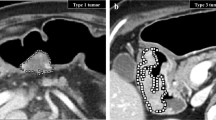

Representative example of pancreatic ductal adenocarcinoma in the uncinate process contiguous with the portal vein. The panel organisation is analogue to Figure 1. A paracoronal reformation was chosen to depict the blind truncation of the common bile duct (ductus hepato-choledochus, DHC) and involvement of the portal vein, which was not apparent on conventional CT. CT with fractal dimension (FD) map of perfusion (left and middle columns with yellow frames, FD colour-code given in the bottom inset) and MRI as reference. A contrast-enhanced, fat-saturated T1 VIBE image (acquired after administration of a gadolinium-based contrast agent) in venous phase (Gd+) is shown to illustrate tumour conspicuity alongside a diffusion-weighted image with b-value = 800 s/mm2 (DWI - b800), which was used for size estimation. The panels with yellow and green frames are magnifications of the tumour area in CT and MRI, respectively, and correspond to the marked areas in the images with original resolution. The hypoperfused tumour core (C, blue dotted line) is depicted in CT and MR (Gd+) images. On CT, no tumour extension to the portal vein was suspected. However, the tumour rim extends into the pancreatic head as seen on MRI and in the FD map (R, high FD mapping values or red dashed line), whereas CT only shows the tumour portion in the uncinate process. Tumour volume was 10 ml on CT, 19 ml on FD map, and 20 ml on MRI. Conventionally measured tumour diameter was 24 mm on axial slices, whereas Feret’s calculated maximum diameter along the longest axis in arbitrary orientation was 32 mm on CT, 47 mm on FD map, and 50 mm on MRI. C, tumour core; R, tumour rim; NP, non-tumourous pancreatic tissue; PV, portal vein; D, duodenum; DHC, ductus hepato-choledochus

Representative example of pancreatic ductal adenocarcinoma in the pancreatic head. A para-axial reformation was chosen to simultaneously depict FD differences in the tumour core, rim, and adjacent non-tumourous pancreatic tissue. The panel organisation is analogue to Figure 1. On CT, the tumour core is the only visible portion of the tumour. In contrast, the tumour rim (R, high FD mapping values or red dashed line) is well depicted on MRI and FD maps and its perfusion pattern is more chaotic than in the tumour core and adjacent non-tumourous pancreatic tissue as indicated by the FD. Tumour volume was 3 ml on CT, 8 ml on FD map, and 9 ml on MRI. Tumour diameter was 18 mm on axial slices, whereas Feret’s calculated maximum diameter along the longest axis in arbitrary orientation was 20 mm on CT, 33 mm on FD map, and 29 mm on MRI. C, tumour core; R, tumour rim; NP, non-tumourous pancreatic tissue; PV, portal vein; D, duodenum; DHC, ductus hepato-choledochus